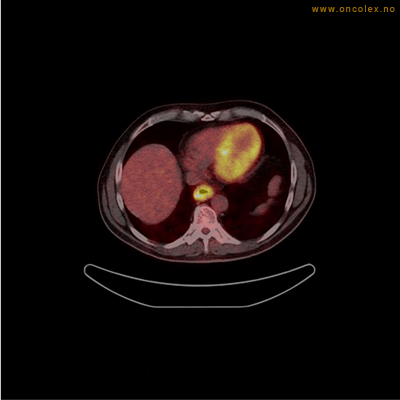

Eksempler på funn

Vev som tar opp mer radioaktivt stoff, synes som hvite områder som lyser opp mer i forhold til annet vev som tar opp mindre sukker.